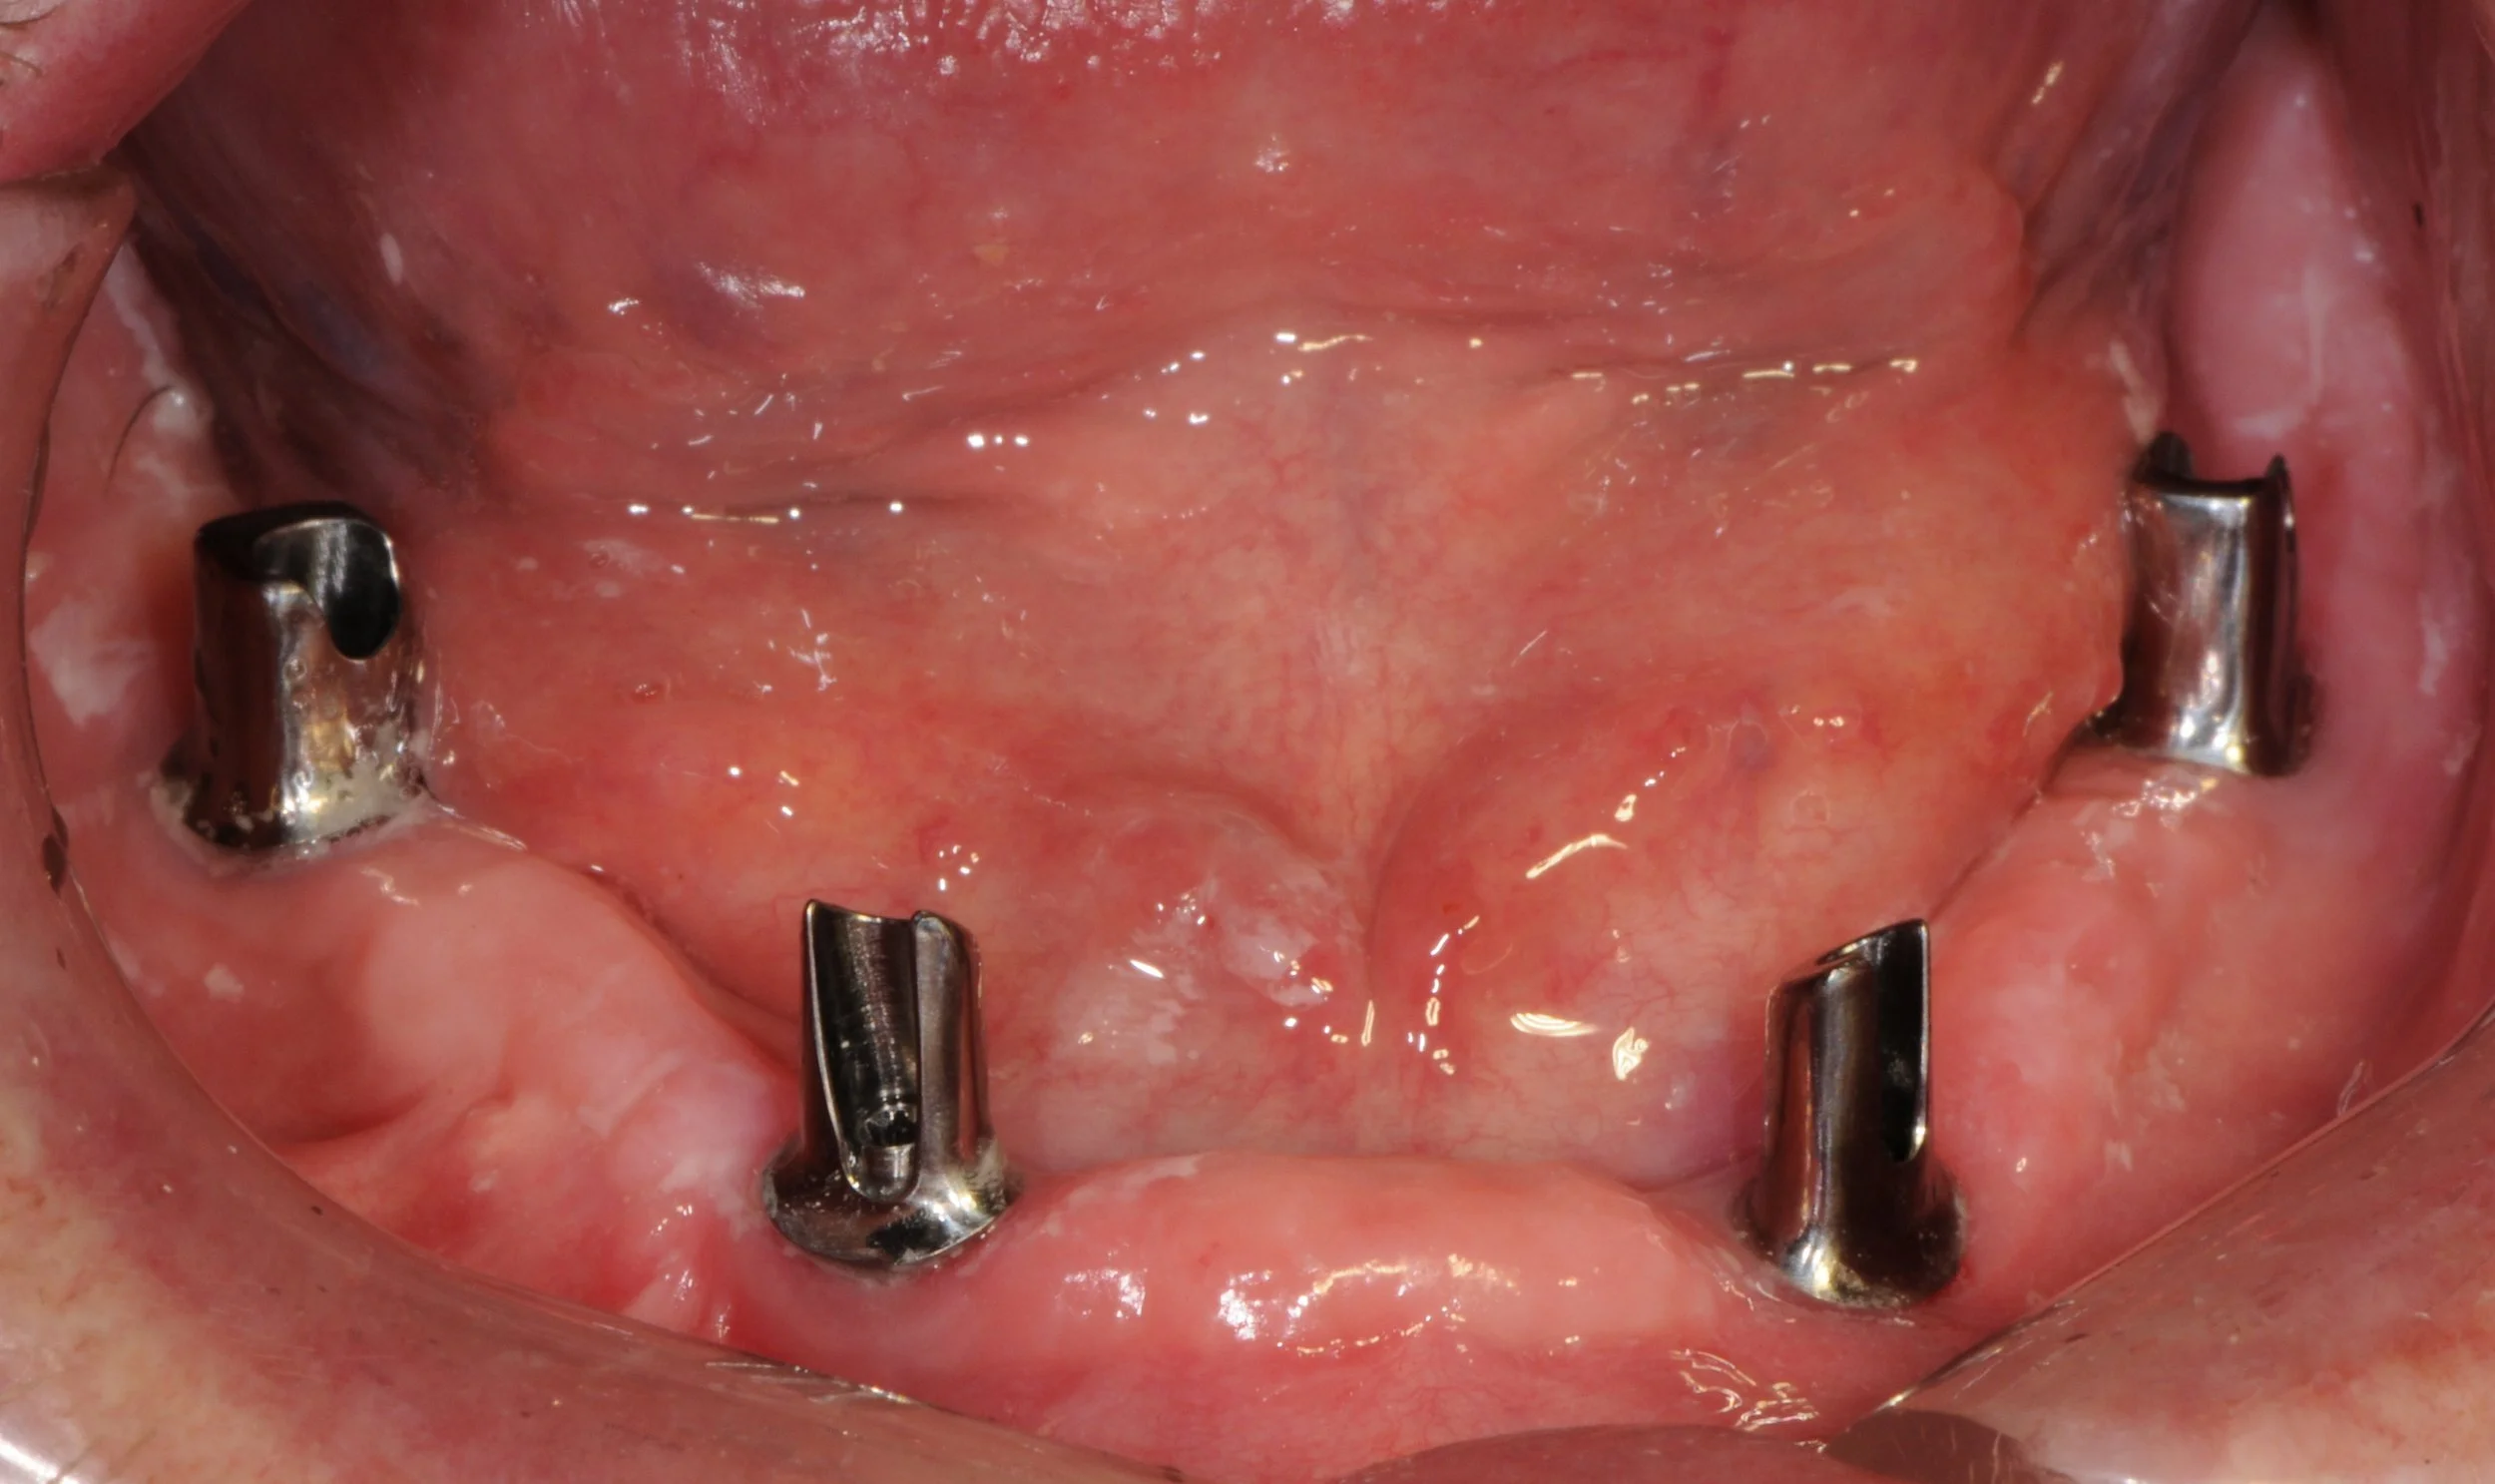

The titanium abutments screwed into the implant fixtures on the lower arch.

-

The titanium Atlantis abutments designed and milled in Sweden to be parallel to each other with a 5 degree taper.

The abutments relative to a replica gum line in a plaster model.